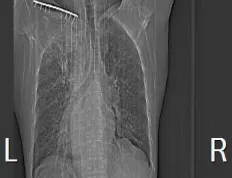

患者王大爷,因出现反复咳嗽、咳痰、喘促症状,入院后经查胸部ct显示左肺占位性病变,但病理性质未明确。为明确病变性质,经与患者及家属沟通同意并充分评估后,医学影像科熊江主任决定行CT引导下经皮肺穿刺活检术,明确肺部病灶性质,为指导下一步诊治提供充分依据。

2.CT扫描,制定穿刺路径,以精确定位穿刺点位置、角度、深度。